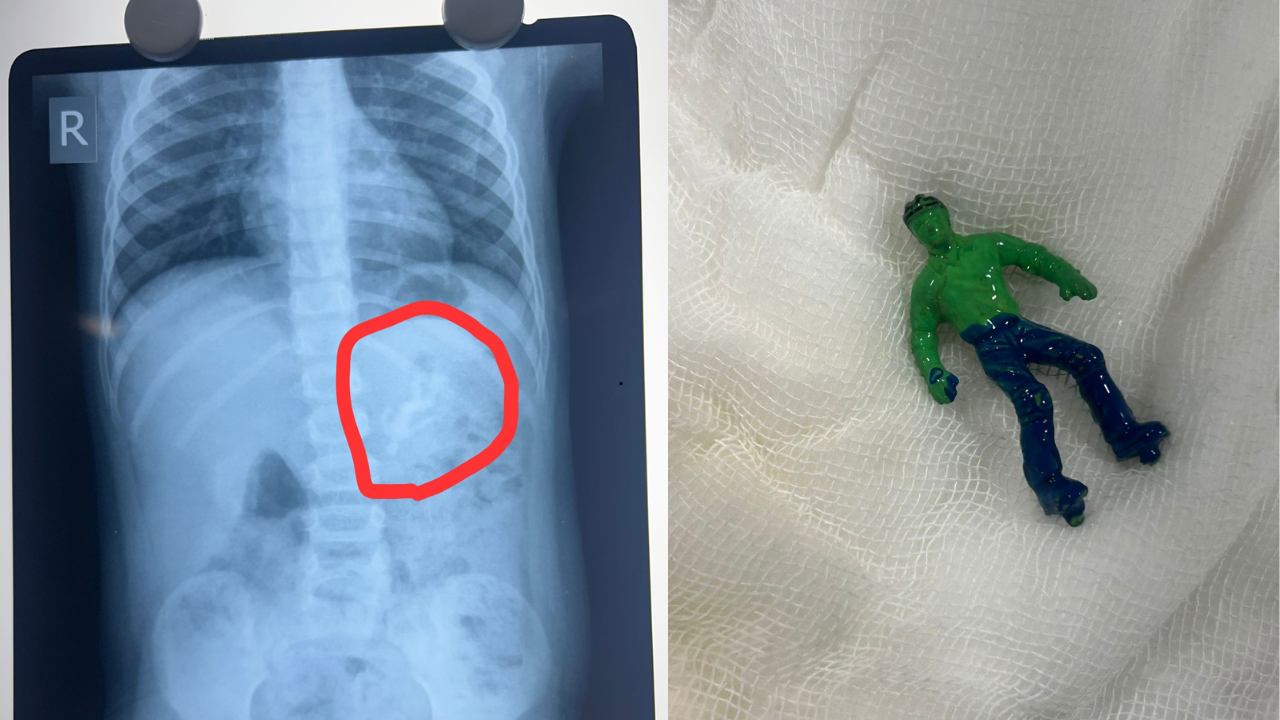

Ahmedabad Toddler Swallows Hulk Toy, Showed X-Ray, Doctors Remove It Via Endoscopy

SummaryA one-and-a-half-year-old Ahmedabad boy swallowed an intact Hulk toy, causing vomiting and discomfort. Doctors removed it endoscopically before serious complications arose. The case highlights choking risks from unsafe toys and underscores the importance of BIS-certified, age-appropriate toys for young children.